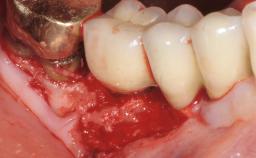

Peri-Implant Tissue Health

Maintenance of healthy peri-implant soft tissue as well as supporting peri-implant bone is an essential part of long-term success of implant therapy. An accurate maintenance protocol of peri-implant tissue health may prevent biological complications such as peri-implantitis. After the delivery of the prosthesis, patients should be followed up and clinical and radiological examinations should be performed on a regular basis to detect any etiological factors that may lead to such complications. This topic discusses properties of healthy and pathological conditions of peri-implant tissue, clinical and radiological examination methods of peri-implant tissue, as well as protocols for maintaining peri-implant tissue health.